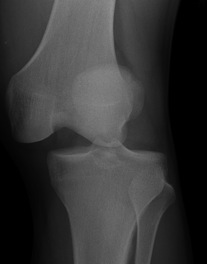

Fibula head avulsion / dislocation

Will typically have LCL and biceps femoris ligament attached

Fibular head avulsion

Fibula head avulsion and medial tibial plateau fracture